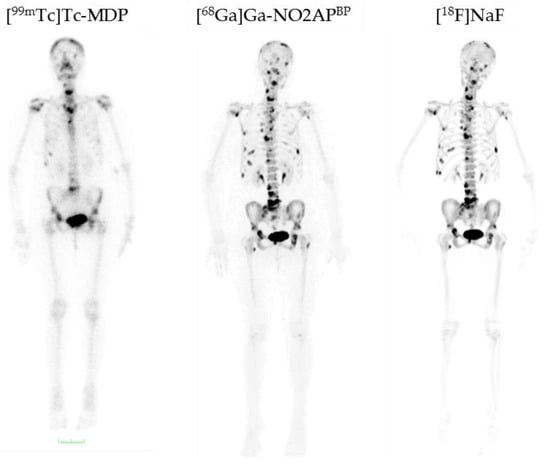

) (6.9 ± 0.1 MBq, n = 4), [68Ga]Ga-BPAPD (

) (9.8 ± 0.2 MBq, n = 8), and [18F]NaF (

) (10.9 ± 0.4, n = 4) in healthy Wistar rats 60 min p.i.